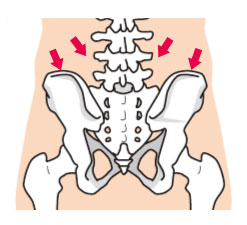

- 腰痛:仙腸関節まわりの癒着を鍼とリリースで緩めることで、立ち上がりの痛みが消失